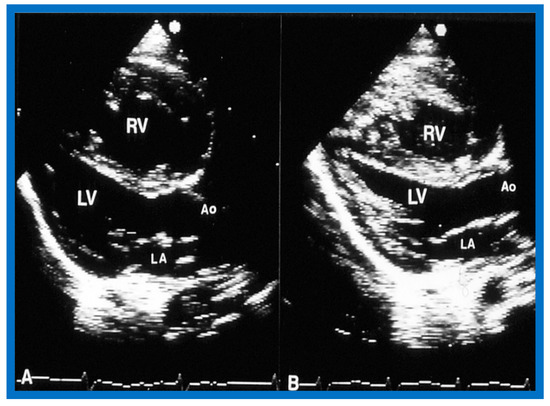

6.1.2. Ventricular Dimensions

6.2.2. Ventricular Dimensions and Function